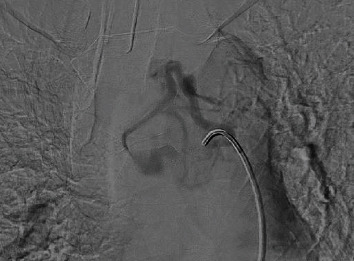

Paraganglioma of the middle mediastinum has a prevalence of 1%-2% of paragangliomas and less than 1% of mediastinal masses. It is generally asymptomatic and can easily be confused with other pathologies. The following is the case of a 50-year-old patient who, as an incidental finding, documented an injury between the aorta and the pulmonary artery, hypervascularized, which was embolized prior to surgery, which facilitated the complete resection of the lesion by sternotomy. With favorable evolution of the patient and discharge on the fourth postoperative day. A thorough review of the literature on the diagnostic and treatment approach to this pathology has been also carried out.

中纵隔副神经节瘤的发病率为副神经节瘤的 1%-2%,不到纵隔肿块的 1%。它一般没有症状,很容易与其他病变混淆。以下是一名 50 岁患者的病例,他偶然发现主动脉和肺动脉之间有损伤,血管扩张,手术前对其进行了栓塞,这有助于通过胸骨切开术完全切除病灶。术后第四天,患者康复出院。此外,还对该病症的诊断和治疗方法进行了全面的文献综述。